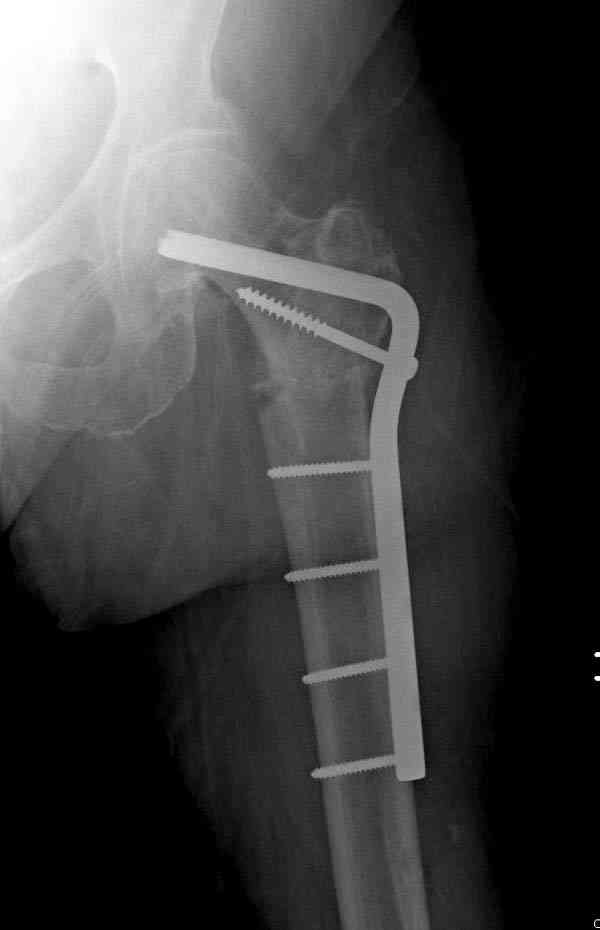

Не стали усложнять интрамедуллярным вариантом коррекции, легче контролировать коррекцию пластиной, поэтому сделали операцию 95 градусной Blade Plate, разогнув до 110 градусов.

Надеемся на успех, потому что до введения пластины дефект от импланта забили костной стружкой и удалось создать компрессию между отломками, максимальную для импланта (150 кило/паунд). Сделана дополнительная костная пластика и за счет измененного угла пластины устранено укорочение конечности.

Допущенные прежним врачом тактические и технические ошибок мы разобрали на нашей конференции по ошибкам "M&M".

Страйкер предоставил отличный инструмент - крючок для удаления длинного гвоздя. Считаем, что врачебная ошибка по установке привела к несостоятельности импланта и к ятрогенному осложнению.